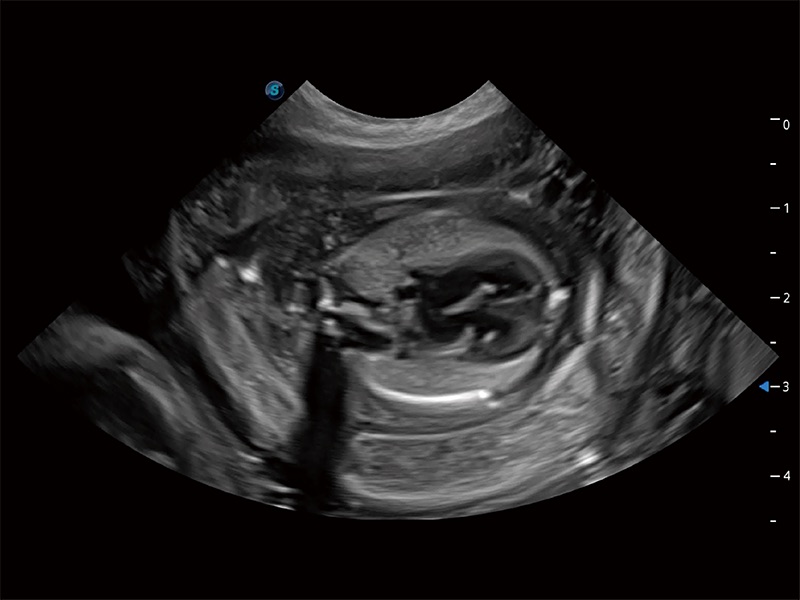

动物是人类最亲密的朋友和最值得信赖的伙伴。诸侯快讯官网也一直致力于探索动物专用的超声影像解决方案。全新推出的ProPet系列,是诸侯快讯官网在动物超声影像智能化、专业化、精准化的一次跨越式革新。动物不能用言语来表述自己的不适,通过超声影像,ProPet系列搭建了动物医生与不同物种沟通的“桥梁”,为动物医生注入了“治愈之力”。 ProPet 80 是诸侯快讯官网匠心打造的一款高端动物专用彩超,采用性能卓越的全新硬件架构,极大提升超声系统的运行效率和数据处理能力,帮助动物医生从容应对日益增多的挑战性病例和日益多样化的临床需求。

高性能和先进的临床应用工具可以为动物医生提供临床信心。ProPet 80 搭载了先进的腹部和浅表应用工具,帮助医生在日常临床实践中发挥前所未有的作用。

ProPet 80 全新的动物超声智能软件和丰富的探头群,为动物医生提供了高清晰度和精细分辨率的图像,无论在宠物、马科、畜牧还是实验室动物等应用中都可以轻松应对,为您的日常工作带来满意的体验。